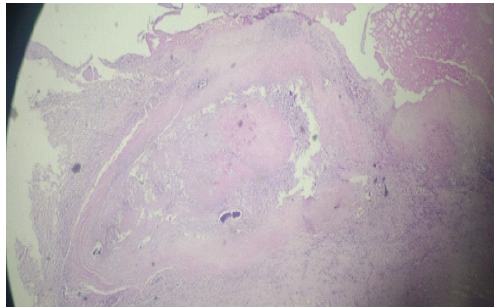

Histopathological examination confirmed chronic granulomatous inflammation with caseous necrosis and multinucleated giant cells, consistent with tuberculosis (Fig. 5).

Figure 5: Low-power view of histopathological section demonstrating chronic granulomatous inflammation with caseous necrosis and multinucleated giant cells.